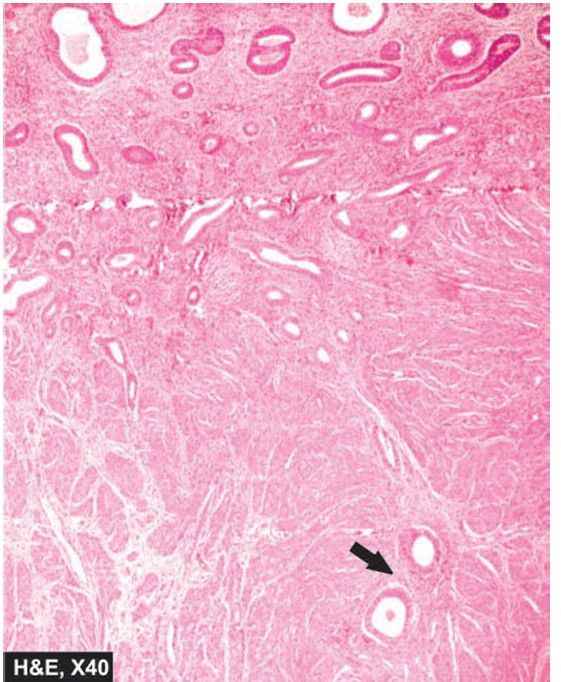

Adenomyosis

The endometrial glands are present deep inside the myometrium (arrow).

Histology

Myometrium